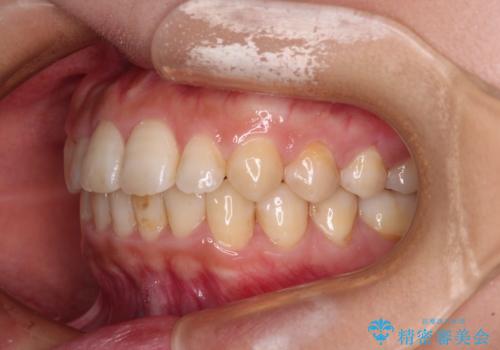

治療前にお伝えした治療期間は1~1年半でして、1年4か月の期間で終えることができました。

ワイヤー矯正は見た目や装置が当たることでの痛みを気にされる方が多いですが、月1回来院して処置をしてもらうだけで歯並びが整うため、大変お勧めです。